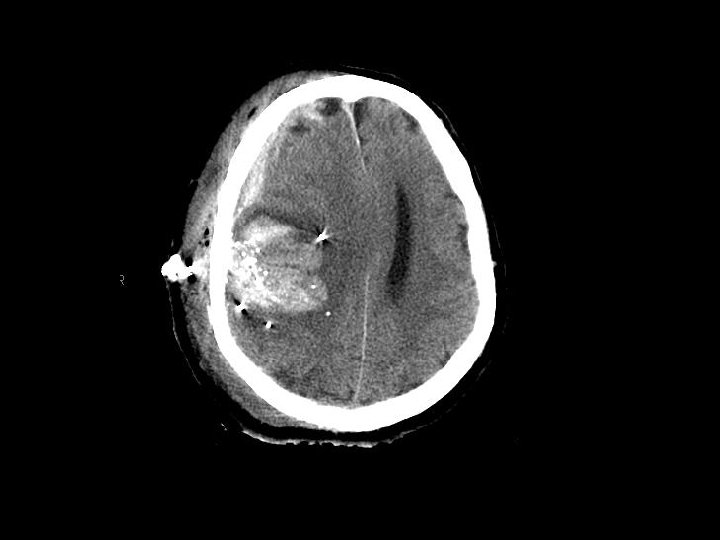

Epidural Hematoma (EDH) • Hemorrhage “above” the dura – Usually arterial (middle meningeal artery) but can also be from venous bleeding • CT: convex (lens shaped) area of blood – Bleeding restricted by the dura’s attachment to the skull • 5 -15% of patients with TBI on CT have an EDH

Epidural Hematoma (EDH) • Potentially rapidly expanding with mass effect and uncal herniation (fixed/dilated pupil) – “Awake and then die” • Most EDHs can be observed • EDHs with mass effect require surgical drainage

Subdural Hematoma (SDH) • Hemorrhage between the dura and the brain – More common than EDH – 30% of patients with TBI have a SDH • CT: Crescent shaped area of blood • Can be acute, subacute or chronic – Subacute or chronic presents days/weeks after injury

Subdural Hematoma (SDH) • Elderly at risk (less severe mechanisms) – Brain shrinks with age resulting in stretching of the bridging veins in the subdural space • May gradually enlarge (slower than EDH) • Surgical drainage for lesions resulting in masse effect and shift